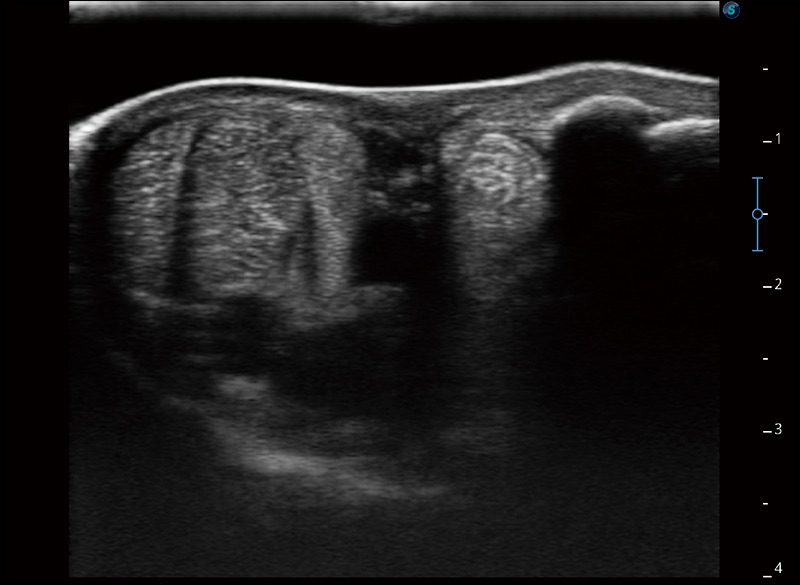

α1卓越的图像质量和便捷的工作流程,使每位宠物医生都能轻松扫查。其全面的兽用应用功能和紧凑型的结构设计,可以满足动物检查的多种需要。专业的预设检查模式和多领域测量软件包有助于为不同类型的动物提供检查, 让宠物医生能够出色的完成工作。

任意波束合成技术

在不牺牲时间分辨率的情况下提供出色的图像

空间复合成像

优化不同角度的图像

扩展成像

支持线阵和凸阵探头,一键操作即可获得更宽的图像视野

实时宽景成像

可实时观察感兴趣区域和病变位置